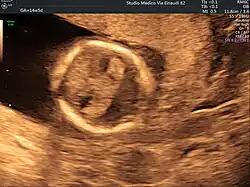

Holoprosencephaly is typically diagnosed during fetal development when there are abnormalities found on fetal brain imaging, but it can also be diagnosed after birth. The protocol for diagnosis includes neuroimaging (Ultrasound or fetal MRI prior to birth or Ultrasound, MRI or CT post birth), syndrome evaluation, cytogenetics, molecular testing, and genetic counseling.[3]